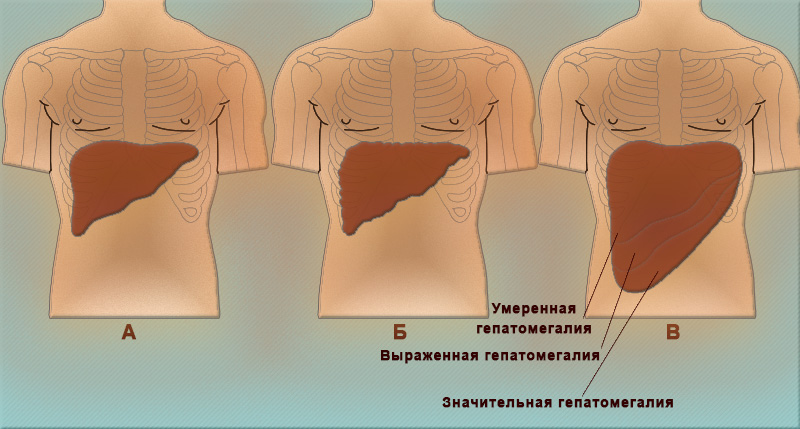

Признаки заболеваний печени: Важные симптомы и рекомендации